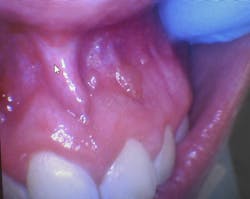

Clinical dental case: Asymptomatic fluid-filled lesions in the vestibular mucosa (nos. 7–10)

Patient presentation: A 17-year-old male patient presented at the initial dental appointment with the following:

Chief complaint: None. The lesions were discovered during a routine oral examination.

Clinical findings:

- Seven asymptomatic, fluid-filled lesions

- Lesions ranged in size from 2 mm to 5 mm

- Lesions similar in color to the surrounding mucosa

- Location: vestibular mucosa, in the region of teeth nos. 7–10

Follow-up appointment: Only three of the original lesions remained.

The presentation of multiple, asymptomatic, fluid-filled lesions on the vestibular mucosa, with a color similar to the surrounding tissue, further supports the likelihood of a mucocele or a mucous retention cyst. The spontaneous resolution of some lesions further strengthens this hypothesis.